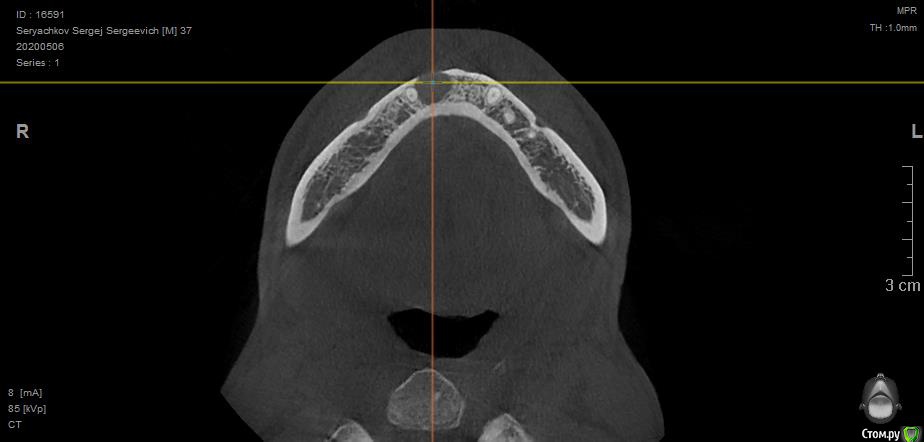

olstrill Опубликовано 24 мая, 2020 Поделиться Опубликовано 24 мая, 2020 Добрый день. Под передними резцами обнаружилась обширная киста. В трёх клиниках предложили различное решение:1. Удаление 2-х поражённых зубов, разбираемся с кистой, ждём полгода, потом вкручиваем Dentium Implantium. На период ожидания верхняя часть вырванных зубов крепится на пластинку, которая как-то крепится на соседние зубы, нагрузка на заглушки до установки имплантов запрещена.2. Удаление 6-ти передних зубов (включая клыки), установка на их место 3-х Dentium Implantium + коронка на 6 удалённых зубов. Врач говорит - как удалим зубы сразу поставим временную коронку, мол эстетически будет самое лучшее решение, а также это самый быстрый вариант, мол пару месяцев - и готово.3. Удаление 2-х поражённых зубов, обточка соседних и установка на шесть передних длинной коронки. Средний вариант по срокам и стоимости. Склоняюсь к первому варианту, но волнуют следующие вопросы:1. Под повреждёнными зубами, как я понимаю, нету или мало кости, в которой можно было бы закрепить импланты. Что там нарастёт за полгода ожидания непонятно. Врач говорит, что нужно будет ещё дополнительно наращивать кость, но не будет ли это половинчатым решением? Подозреваю, что импланты будут подвижны, что, как я понимаю, не хорошо.2. Импланты в зоне улыбки могут эстетически выглядеть не очень, к тому же могут просвечивать через десну.3. Будут слабо выражены переходы между имплантами, десна там может принять прямую форму, что эстетически будет смотреться так себе.3. Временные зубы на месте вырванных на период восстановления кости, врач говорит - периодически будешь приходить и будем править тебе пластинку с "заглушками". Думаю потеряю я эту пластинку в первую неделю и буду ходить полгода с дырой впереди (что, в связи с работой, неприемлемо). Хотелось бы услышать мнение экспертов - правильные ли предложены методы решения проблемы и обоснованны ли переживания. Ссылка на комментарий